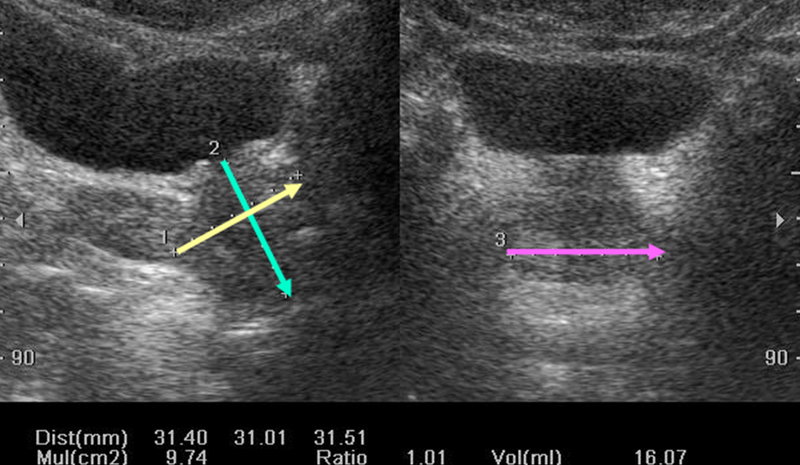

Siêu âm vùng chậu là phương pháp chẩn đoán hình ảnh không xâm lấn nhằm quan sát các cơ quan nằm trong vùng chậu. Thông thường bác sĩ có thể yêu cầu thực hiện kỹ thuật này để chẩn đoán tình trạng sức khỏe vùng chậu hoặc kiểm tra thai khi còn trong bụng mẹ. Vậy siêu âm vùng chậu là gì?

Siêu âm vùng chậu là kỹ thuật được áp dụng phổ biến nhằm mang đến những hình ảnh về các cơ quan và cấu trúc vùng chậu. Nếu đối tượng siêu âm là phụ nữ thì vùng chậu cần kiểm tra bao gồm âm đạo, tử cung, cổ tử cung, ống dẫn trứng và buồng trứng. Với nam giới, kỹ thuật siêu âm này giúp kiểm tra, chẩn đoán các vấn đề liên quan đến túi tinh, tuyến tiền liệt và bàng quang.

Siêu âm vùng chậu hay còn gọi là siêu âm vùng bụng dưới, siêu âm qua ổ bụng, siêu âm phụ khoa, siêu âm qua âm đạo… là một kỹ thuật chẩn đoán hình ảnh không xâm lấn nhằm tạo ra hình ảnh để bác sĩ đánh giá các cơ quan và cấu trúc bên trong khung chậu.

Kỹ thuật siêu âm này sử dụng đầu dò truyền sóng âm ở tần số cao thường áp dụng khi siêu âm thai kỳ. Sóng siêu âm từ đầu dò dội vào các cơ quan và mô trong cơ thể, sau đó dội ngược trở lại đầu dò. Sóng âm truyền đến máy tính chuyển đổi thành hình ảnh các cơ quan và hiển thị trên màn hình vi tính.

Siêu âm vùng chậu có thể được tiến hành bằng một trong hai phương pháp gồm siêu âm ổ bụng hoặc qua âm đạo. Để có được đầy đủ thông tin cần thiết cho chẩn đoán hoặc điều trị bệnh, bác sĩ có thể sử dụng một hoặc cả hai phương pháp.

Bác sĩ chẩn đoán hình ảnh sẽ phân tích hình ảnh siêu âm và gửi trả kết quả cho người bệnh. Thông qua kết quả, bác sĩ điều trị sẽ thấy được những bất thường liên quan đến vùng chậu, mạch máu hoặc tình trạng của thai nhi (nếu có).